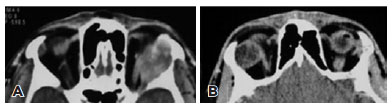

The clinical and radiologic findings of the11 PAs and 16 ACCs were evaluated (Tables 1-2). There were no significant differences between groups in terms of age or sex. Although there was no significant difference in terms of proptosis, palpable mass, diplopia, sensory loss, or persistent pain between PAs and ACCs, these clinical symptoms were observed relatively more often in ACCs in our study. The mean duration of symptoms was significantly longer in the PA group (p=0.001);notably, duration was longer than 120 months in 5 patients with PA. Proptosis was the most common presenting symptom in both groups (90% in PA vs. 87.5% in ACC).All lacrimal gland lesions were isointense relative to extraocular muscle on CT. There were no statistically significant differences in terms of homogeneity and globe indentation between lacrimal gland PAs and ACCs on CT (p>0.05). Bone invasion, wedge sign, and calcification were observed significantly more often in ACCs, while bone remodeling was significantly more common in PAs on CT (all p<0.05). PAs were significantly more likely to show well-defined margins, lobulated contour, heterogeneous contrast enhancement, and hyperintensity on T2-weighted MRI (all p<0.05; Figures 1-2).

11-fig01.jpg)

All PAs showed well-defined margins on CT imaging, which is animportant sign for distinguishing benign from malignant tumors of the lacrimal gland. ACC has been reported to have poorly defined margins in the literature(7,9,22,23). ACCs are also more likely to have a tail or wedge sign than PA, indicating infiltration into the posterior orbit. A triangle of tissue between the lateral rectus and lateral orbital wall or between the superior rectus and orbital roof is termed the wedge sign, and commonly appears in lacrimal gland carcinoma(24). In our study, the wedge sign was observed in 14 of 16 patients with ACC. Calcification and bone invasion of masses of the lacrimal gland usually suggest malignant disease(21). In our study, tumor calcification and bone invasion were observed on CT more frequently in ACC than PA (62% vs. 9% and 44% vs. 0%, respectively). In the literature, bone invasion is reported at rates of 45-82% in ACC(22,23,25). Although patients with long-standing large PA may show modulation of the bony area of the lacrimal fossa without periosteal disruption (bone remodeling), this should not be considered bone invasion. Bone remodeling consists of displacement and, in most cases, thinning of bony walls. It is observed in benign neoplasms, in some chronic inflammatory lesions, and rarely in malignant neoplasms(26). Several products of malignant cells directly and indirectly cause resorption of bone and allow invading tumor cells to grow into the reabsorbed space during the bone invasion process(27). On CT, bone remodeling is observed as thinning and displacement in the lacrimal fossa, whereas bone invasion is observed as destruction in the lacrimal fossa. In our study, bone remodeling was observed in 81% of patients with PA and 31% of patients with ACC. In the literature, the rates vary widely from 14 to 84% in PA(6,7,13).